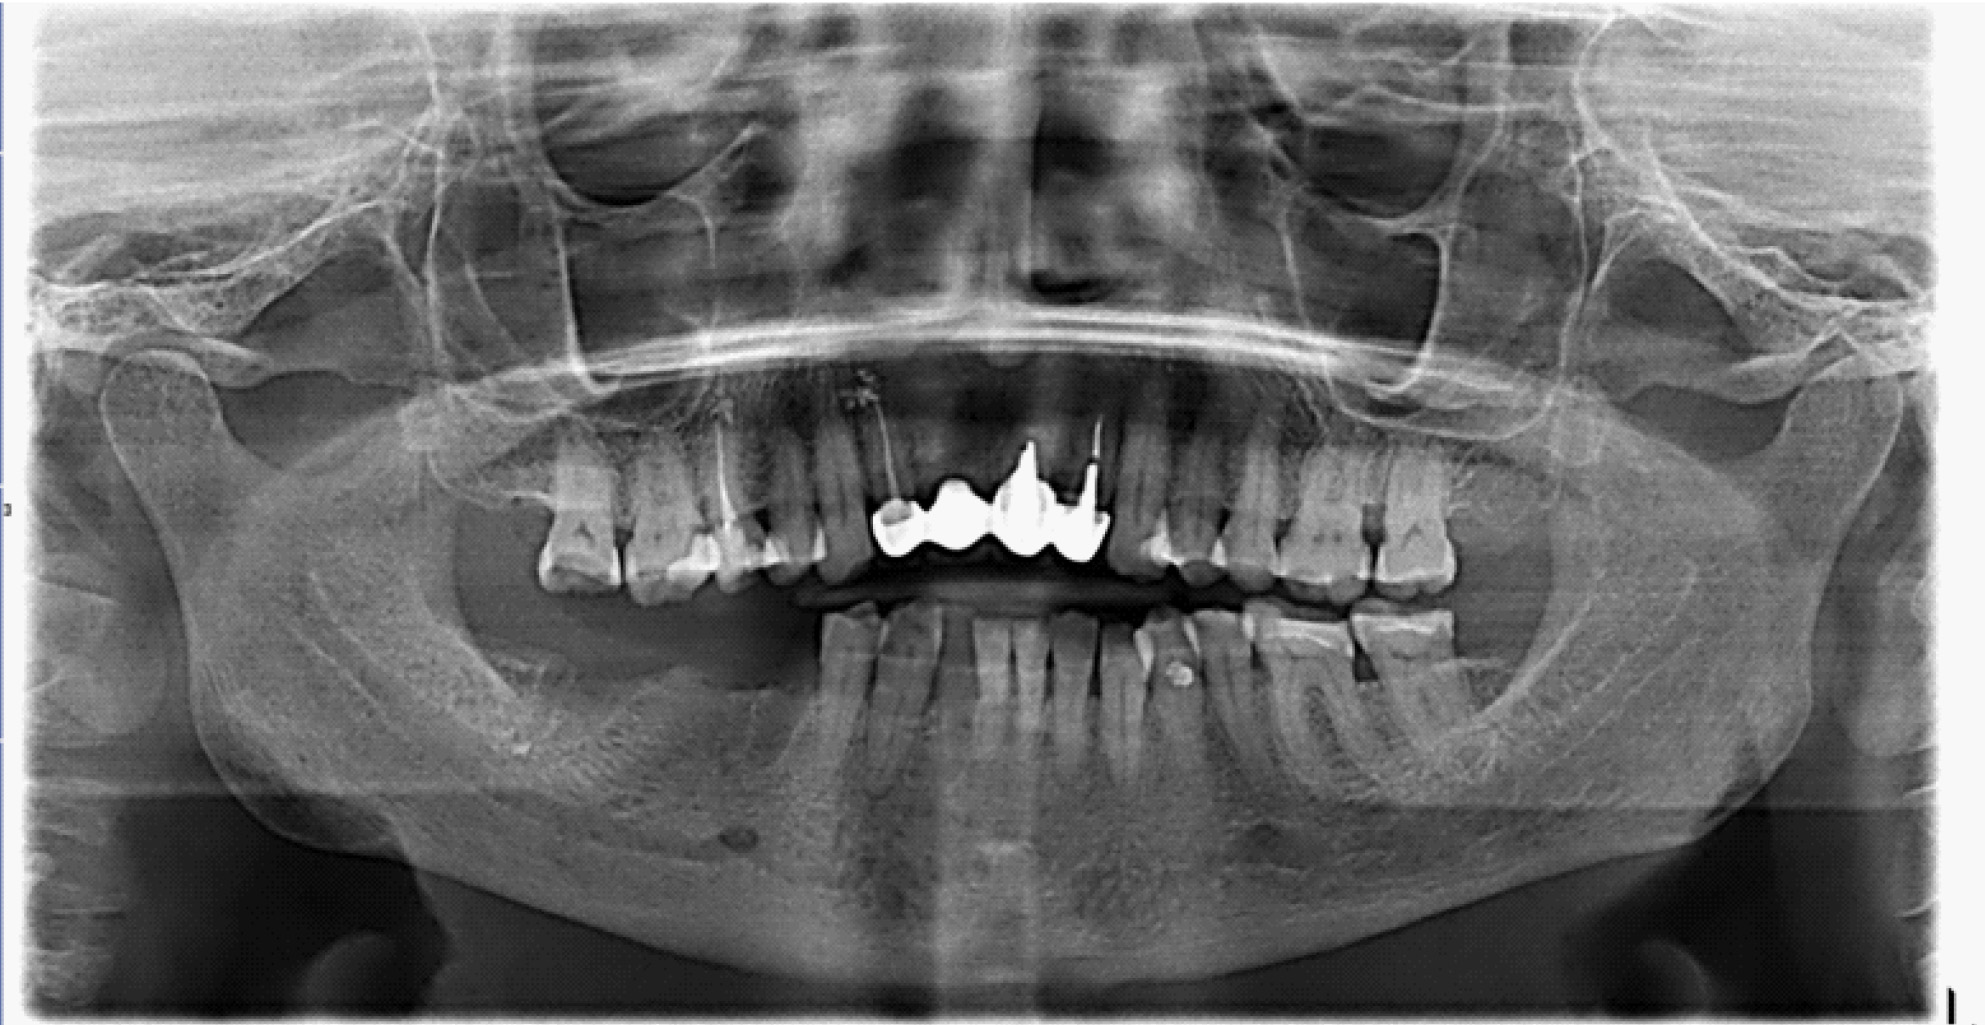

В полости рта: нарушение целостности слизистой оболочки полости рта, субтотальный остеонекроз альвеолярной части нижней челюсти слева. Вид костной тканей серо-коричневого цвета, пальпация безболезненная. На ортопантомограмме отмечается ограниченный участок деструкции костной ткани нижней челюсти с поражением тела нижней челюсти. Одонтогенной причины заболевания нет (рис. 1).

Рис. 1. Клинические проявления бисфосфонатного остеонекроза нижней челюсти во фронтальном отделе